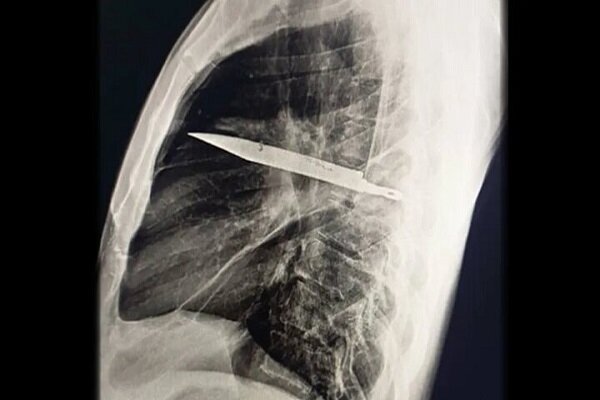

تصویربرداری با اشعه ایکس و سیتیاسکن نشان داد تیغهایچ بزرگ از چاقو از پشت قفسه سینه وارد شده، بین دندههای پنجم و ششم گیر کرده و نوک آن تا جلوی قفسه سینه بین دندههای سوم و چهارم امتداد یافته است. شکستگیهای ترمیمشده در استخوان کتف و چند دنده نیز مشاهده شد. همچنین اطراف تیغه، بافت مرده و چرک تجمع یافته بود.